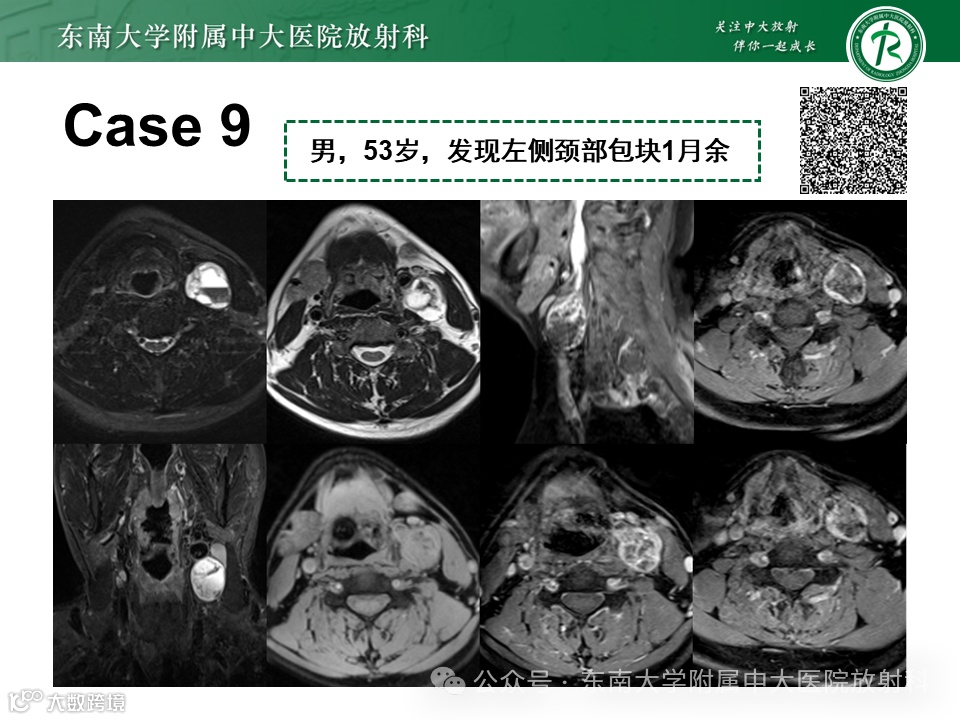

病例3.2:左侧颈部副神经节瘤(颈动脉体瘤)